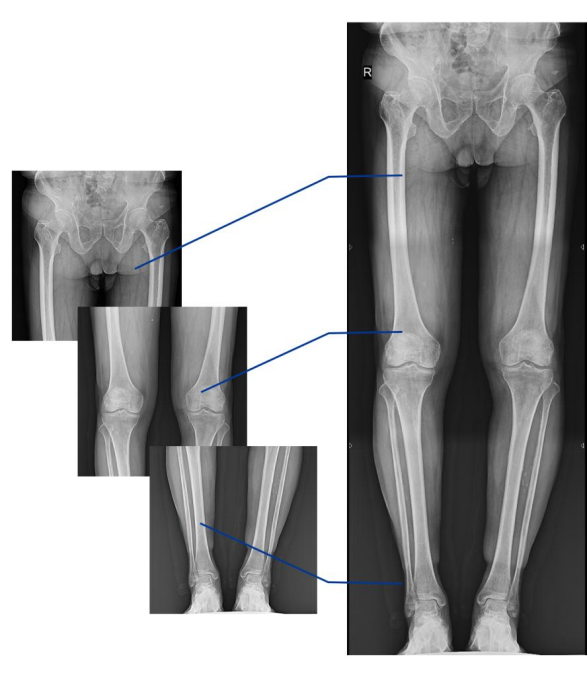

不同于常规静态DR只能进行平片摄影检查,动态DR可以满足多种临床检查需求,包括静态检查、透视检查、造影检查、脊柱及下肢全长拼接检查,相较于静态DR具有丰富的临床应用,且动态DR检查更精准、直观,摆位摄片效率极大地提升,大大节省拍片时间。

动态DR影像采集幅面大,17×17英寸超大视野,可覆盖成年人的全胸全腹,并且能在连续动态中实时高清点片,还可以进行视频保存,在会诊过程中可以回放影像检查视频,从而达到精准诊断的目的。同时动态DR还具有全身拼接功能,尤其适用于全脊柱和全下肢摄影,辅助脊柱畸形矫形治疗、康复检查,为临床提供高精度图像。